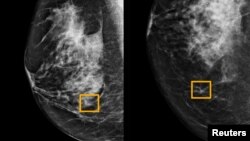

Quiz - Google System Could Improve Breast Cancer Detection

What did the study find about Google’s artificial intelligence (AI) and breast cancer detection?

The Google system detected breast cancer as effectively as expert radiologists.